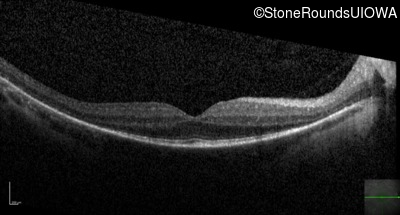

Optical Coherence Tomography - Left - 20/32 -1

Exemplar / OCT Stack

OCT Stack